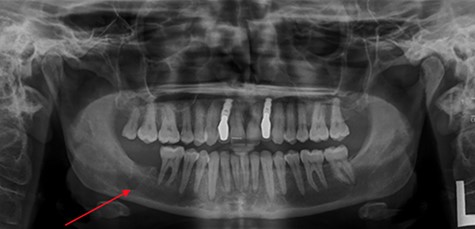

A 37-year-old fit and well lady presented to her General Dental Practitioner (GDP) complaining of pain in the right side of her mandible and episodic numbness in the ipsilateral mental nerve distribution. An orthopantomogram (OPG) (Fig. 1) was taken, with the GDP contentiously identifying an area of increased radiolucency at the apex of the right lower second molar. The patient was referred to a specialist dentist for root canal treatment of the tooth, with the GDP suspecting irreversible pulpitis.

OPG taken on patient’s first visit to GDP. Demonstrates radiolucency at apex of LR7.